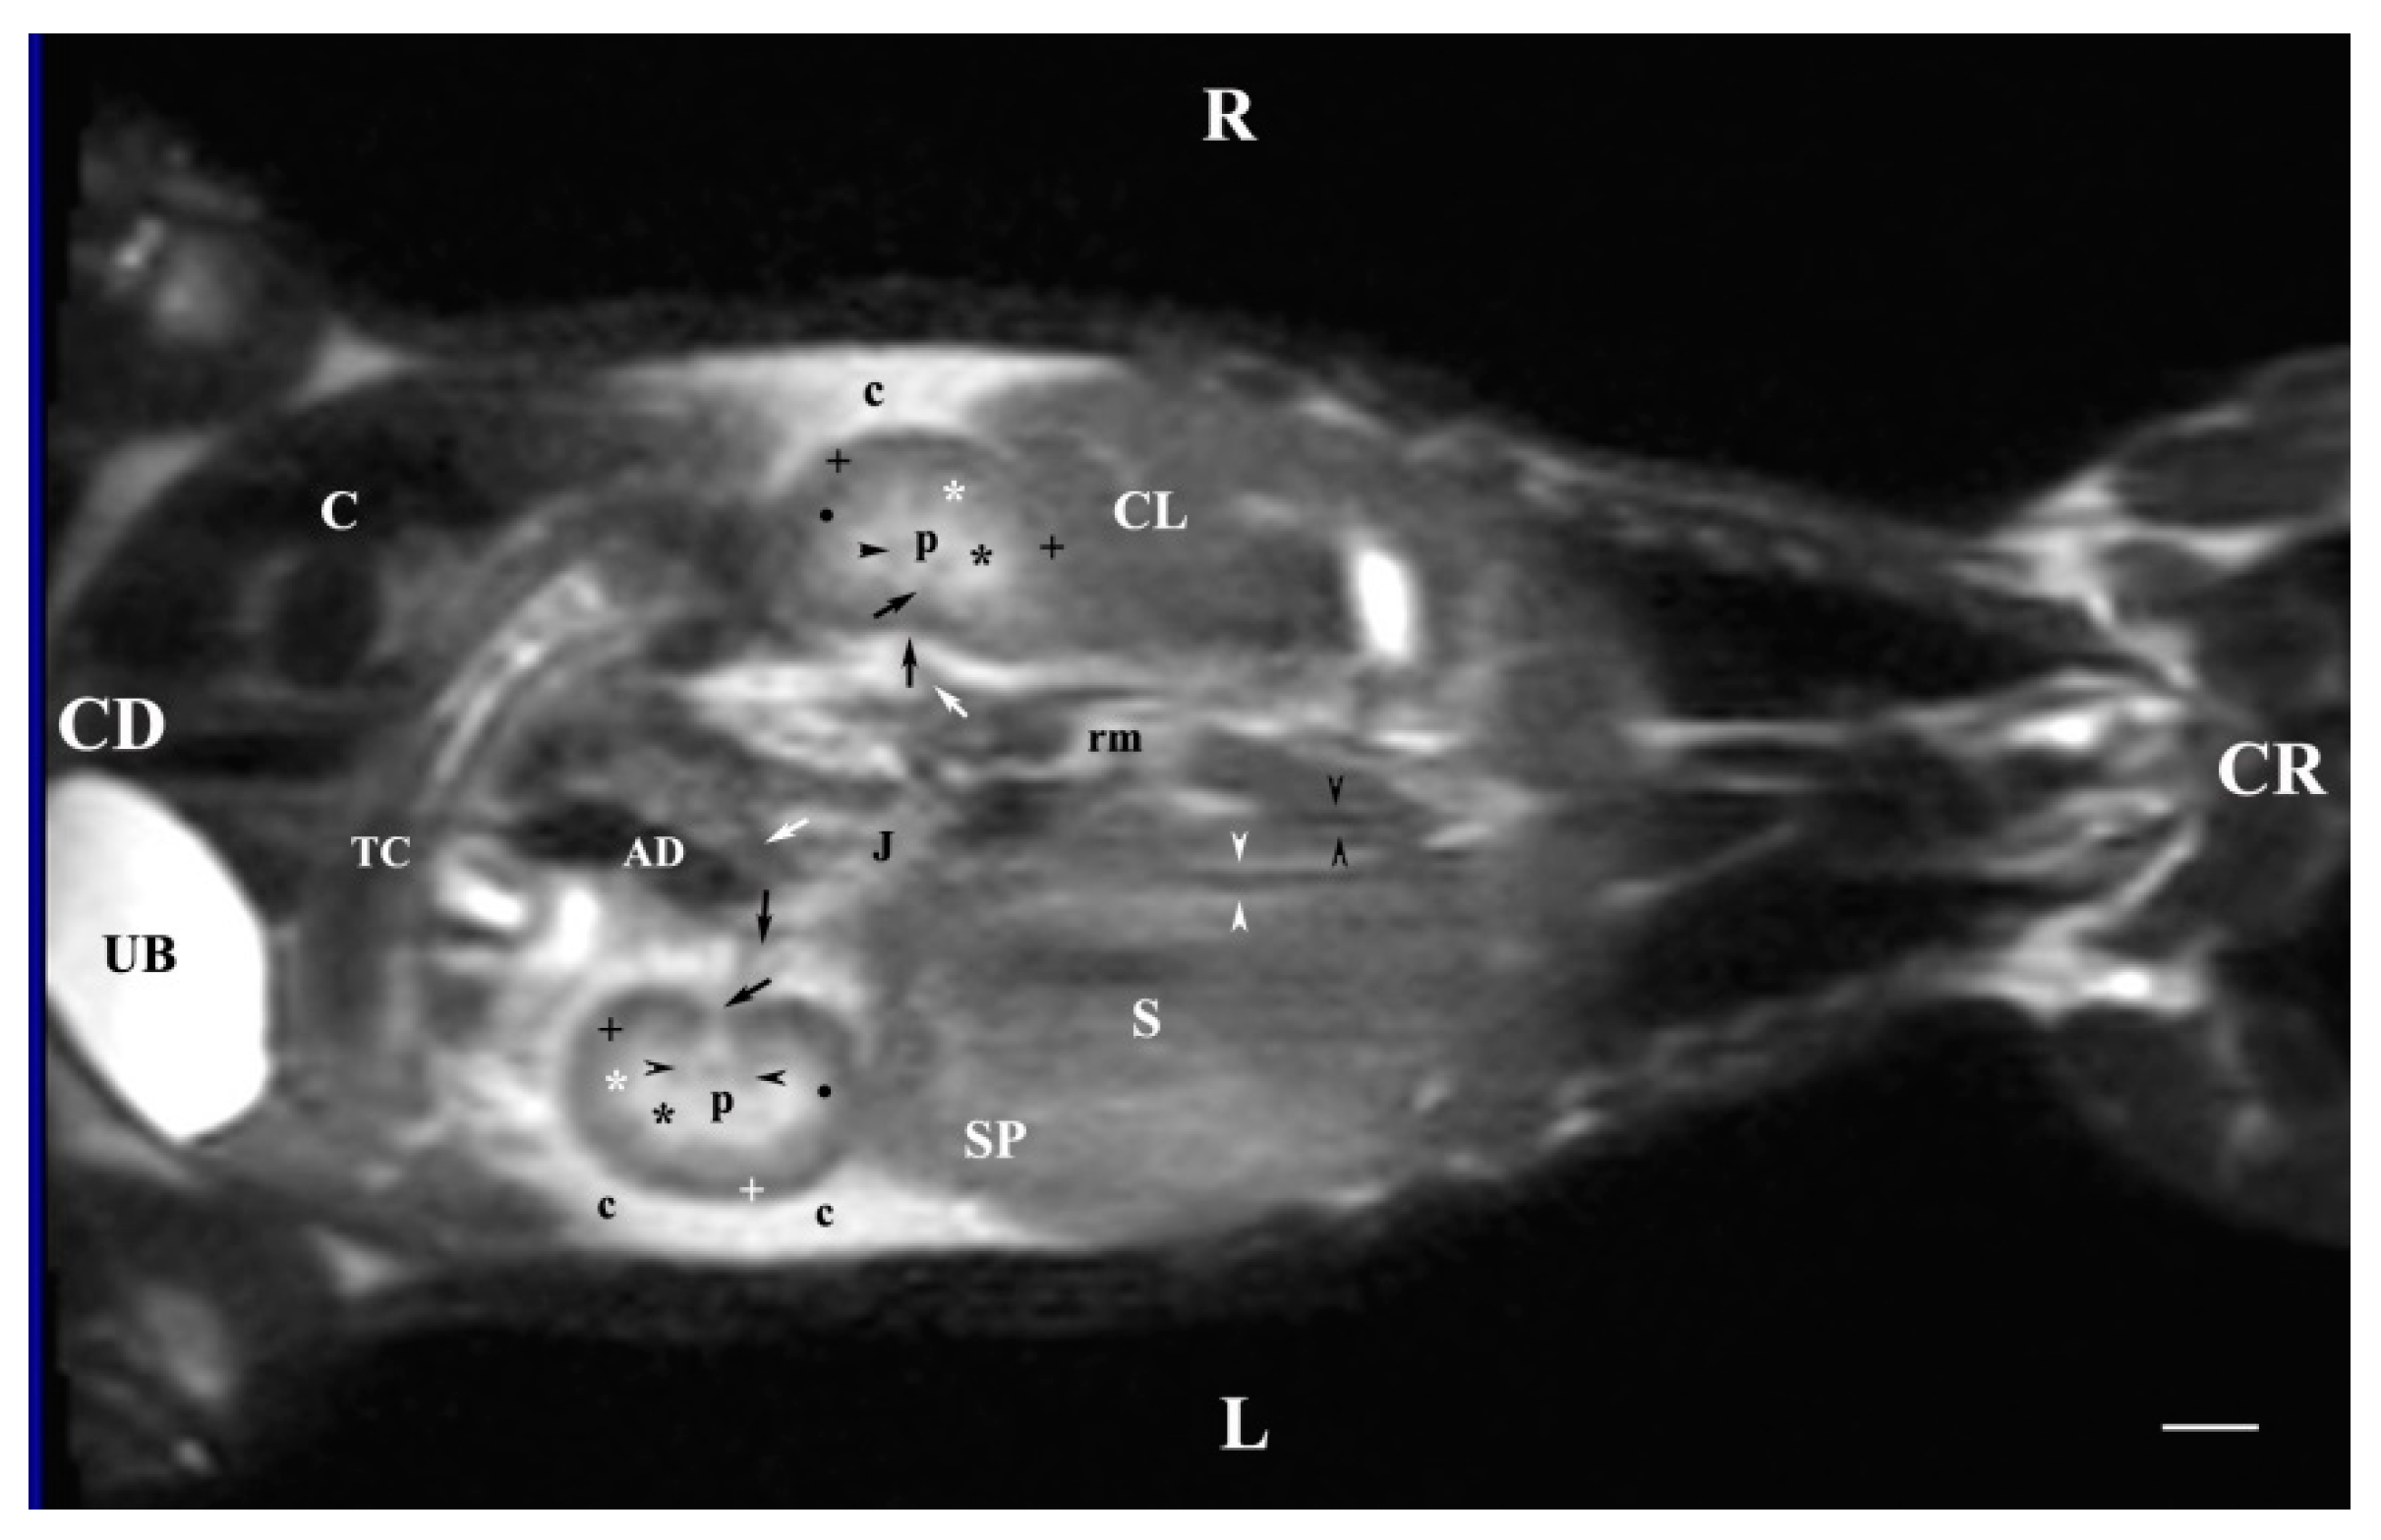

3.2. Sagittal MRI